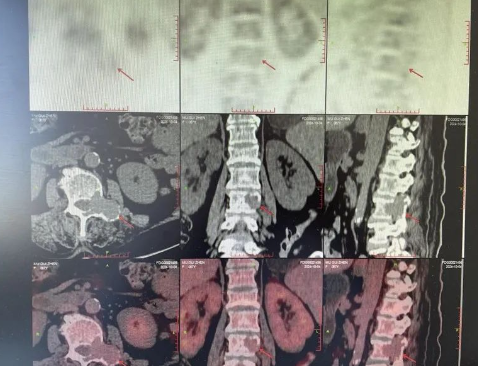

品質(zhì)國文丨追蹤腫瘤的“高精雷達(dá)”-PET/CT

PET/CT,被譽為腫瘤病灶追蹤的“高精雷達(dá)”、“生命衛(wèi)士”,作為健康體檢的高端手段之一,其優(yōu)勢在于既可顯示人體組織臟器的精確解剖圖像又能同時顯示人體組織、細(xì)胞的代謝功能圖像。 閱讀量:2417